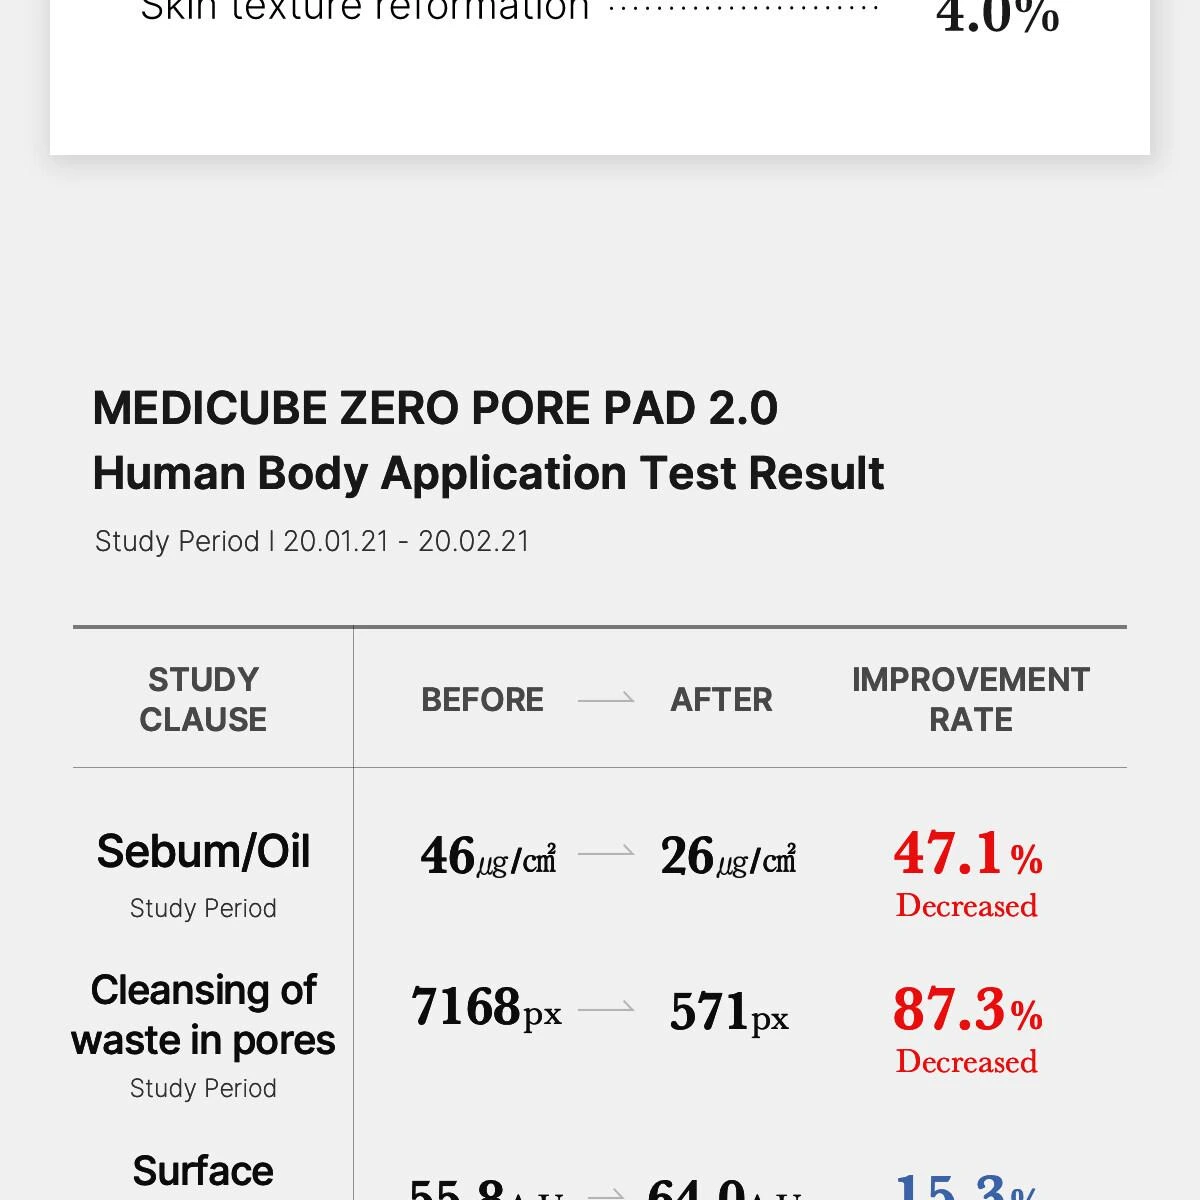

Idéal pour les peaux sujettes aux pores dilatés, à l’excès de sébum, aux points noirs, aux points blancs ou à une texture irrégulière, ce soin permet de réduire visiblement les pores, de limiter leur obstruction et d’améliorer l’hydratation de la peau. Les résultats sont prouvés : diminution du sébum jusqu’à 47,1 %, réduction des impuretés dans les pores jusqu’à 87,3 %, amélioration de l’hydratation et meilleure tenue du maquillage. Véritable best-seller de la K-Beauty avec plus de 400 millions d’unités vendues, ce produit est reconnu comme le pad resserre-pores numéro 1 de MEDICUBE.